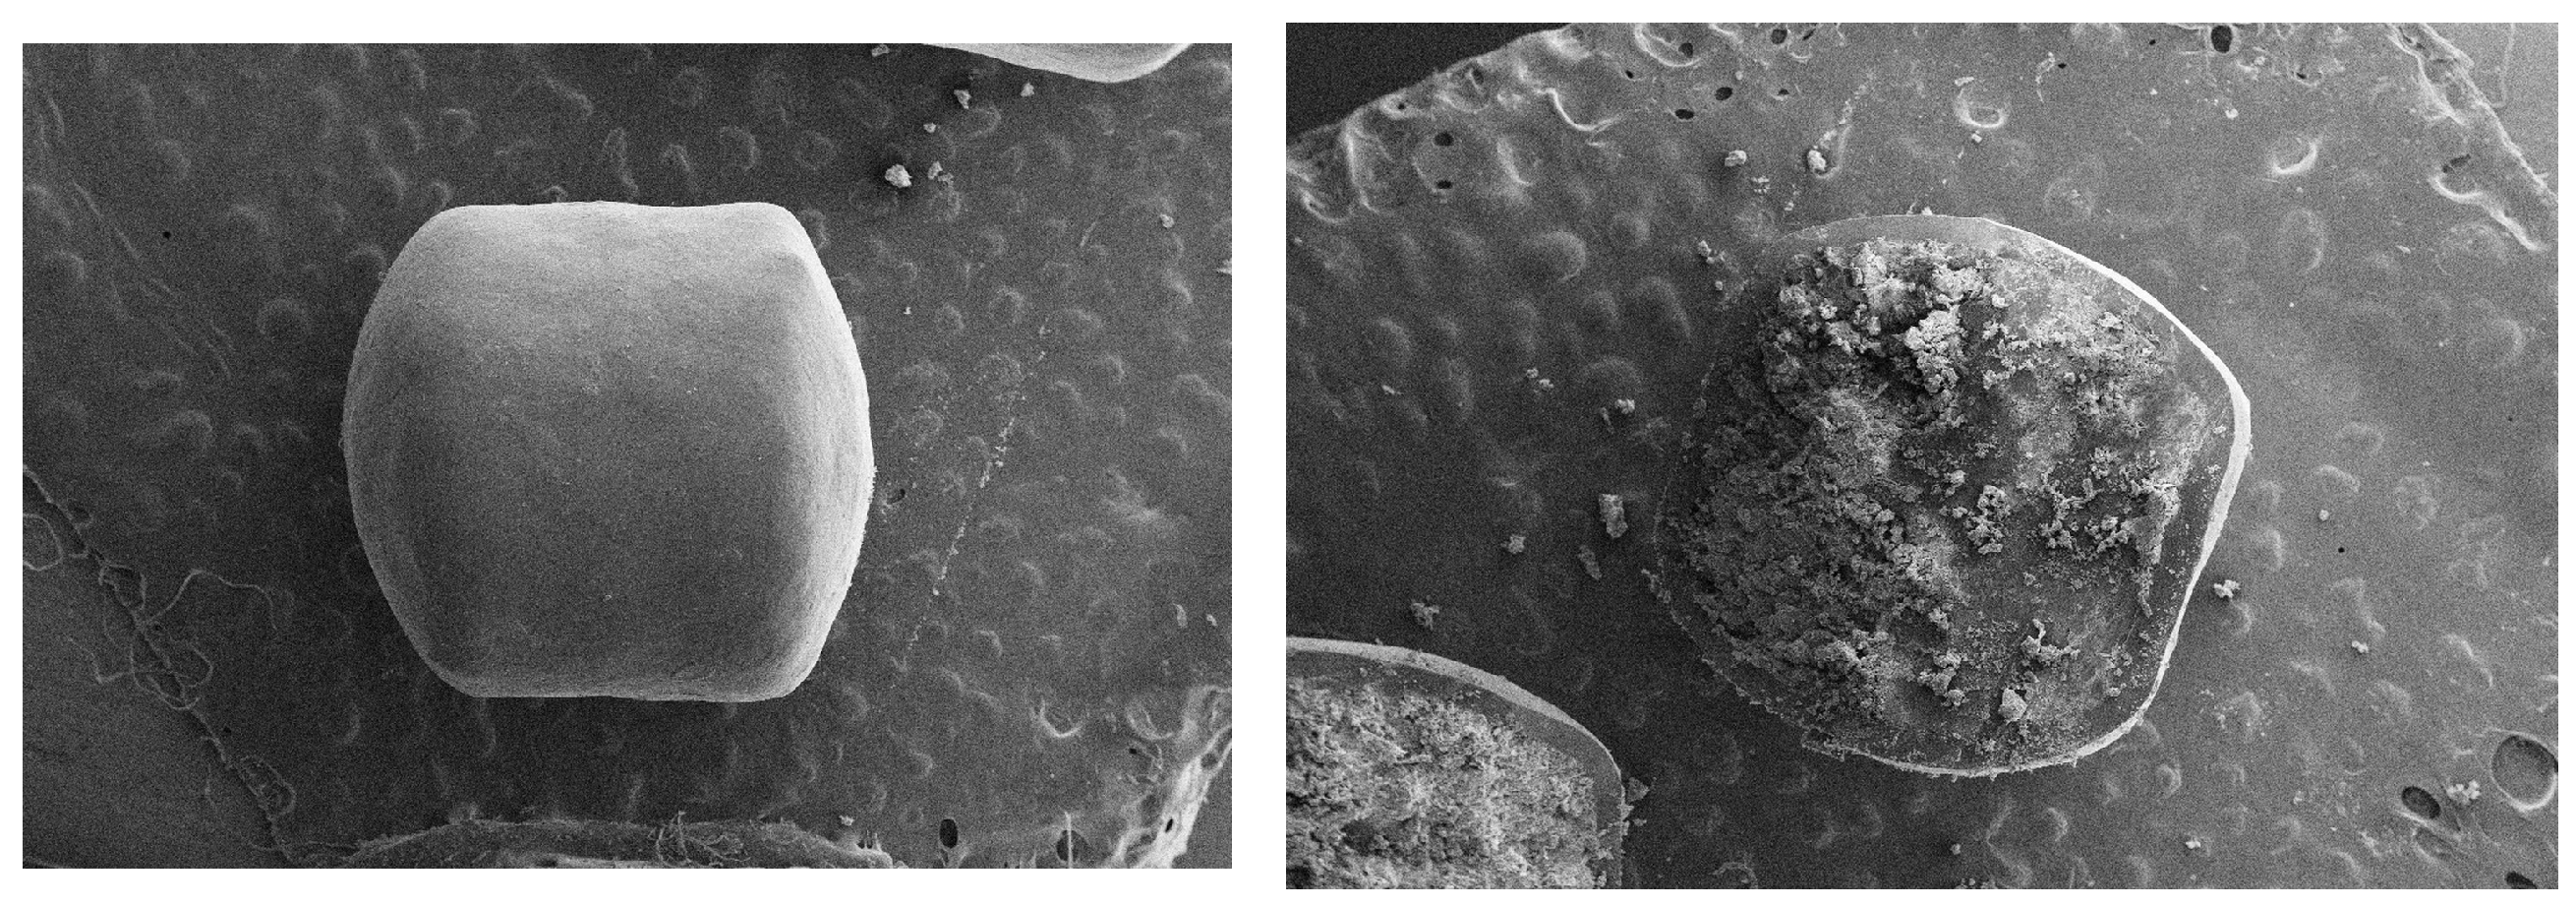

2.2.4. Scanning Electron Microscopy (SEM)

3.2.1. EC Pellets

3.2.2. Mini-Tablets and Normal Tablets